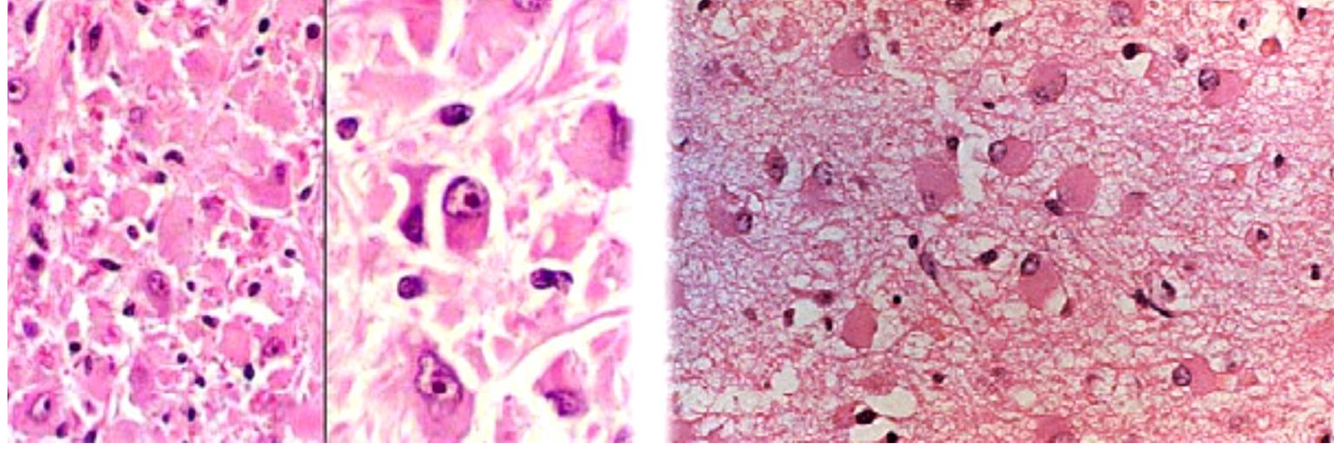

What does spongiform change look like on histology?

neuropile vacuolization (seen in Mad Cow disease and Creutzfeldt-Jakob disease)

+ gliosis - increased glial cells with observable nuclei

neuron swelling with foamy, vacuolated cytoplasm due to lipid accumulation within lysosomes

45